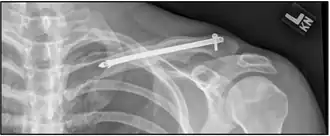

![]() | |

| X-ray of a left clavicle fracture | |

A discontinuity in the bone shape often results from a clavicular fracture, visible through the skin, if not treated with surgery. Surgical procedures often call for open reduction internal [plate] fixation where an anatomically shaped titanium or steel plate is affixed along the superior aspect of the bone by several screws. In some cases, the plate is removed after healing due to discomfort, to avoid tissue aggravation, osteolysis or subacromial impingement. This is especially important with a special type of fixation plate called hook plate.[17] With anatomical plates plate removal is considered an elective procedure that is rarely necessary. An alternative to plate fixation is elastic TEN intramedullary nailing. These devices are implanted within the clavicle's canal to support the bone from the inside. Typical surgical complications are infection, loss of sensation distal the incision due to inadvertent injury of one or several supraclavicular nerves (most common when using a horizontal surgical incision)[18], and nonunion of the bone (failure of the bone to properly fuse together). Major nerve injury to the brachial plexus or vascular injury is extremely rare.[19]